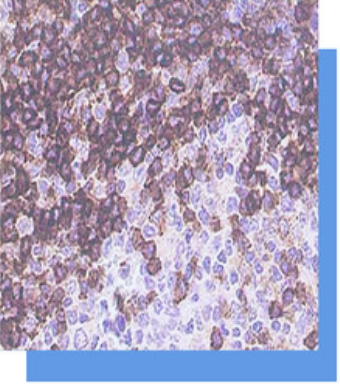

CD45R是CD45的异构体,家族由限制性形式的

白细胞抗原组成,分成4个异构体: CD45RA.

CD45RB、CD45RC和CD45RO。 CD45RA主要

表达在B淋巴细胞,部分胸腺髓质细胞。此抗体

可以识别大多数的B细胞及B细胞淋巴瘤。常与其

他B细胞标记物CD20和CD45RB联合检测,主要

用于B细胞淋巴瘤的辅助诊断。